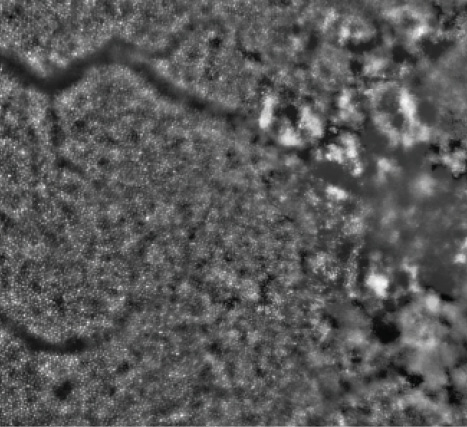

Figure 4. AO image of the eye with CSCR shown in Figure 2, taken in a region nasal to the fovea and magnified to show the mosaic of individual photoreceptors.